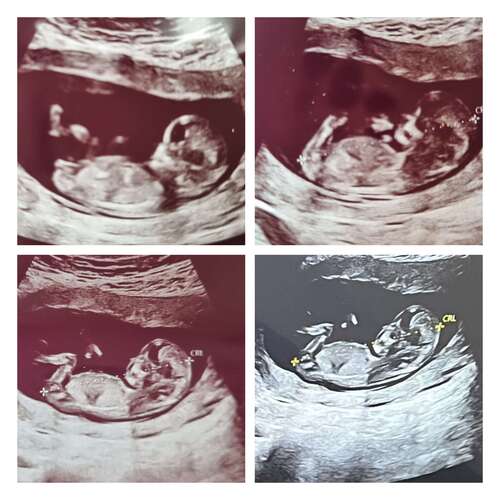

Ik ben ook benieuwd dit is 12 weken. Alleen ik zie het niet haha

Wat denken jullie? 12 weken💗💙

💕 meisje..

Echo met 11+3. Wat denken jullie? 🤗

Tot nu toe een meisje, ze zeggen dat je met 12+4 75% betrouwbaarheid hebt.. dus het kan nog naar een jongen veranderen.